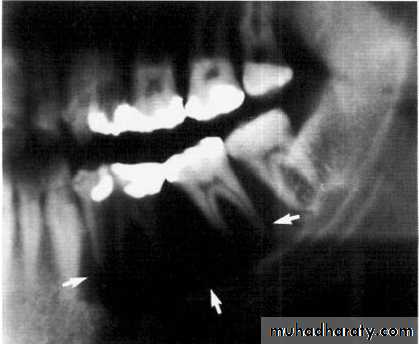

Central giant cell granuloma*A relatively uncommon, non- neoplastic mass in the jaws (intraosseous) producing an expansile radiolucent soap bubble appearance.

*Age; <20 years. Female > Male.

*Teeth are vital, with some root resorption & migration of teeth.

Multilocular appearance, expansion (arrowed) and considerable displacement of the adjacent teeth.

Buccal and lingual expansion (arrowed) and the undulating cortical border.

• Aneurysmal Bone Cyst

Large multilocular aneurysmal bone cyst

in the ramus with marked expansion andthe displacement of/8.

It is non-neoplastic ,exaggerated , localized, proliferative lesion of vascular tissue, containing giant cells.

It’s a variation of the central giant cell granuloma , can be diagnosed only by histological examination